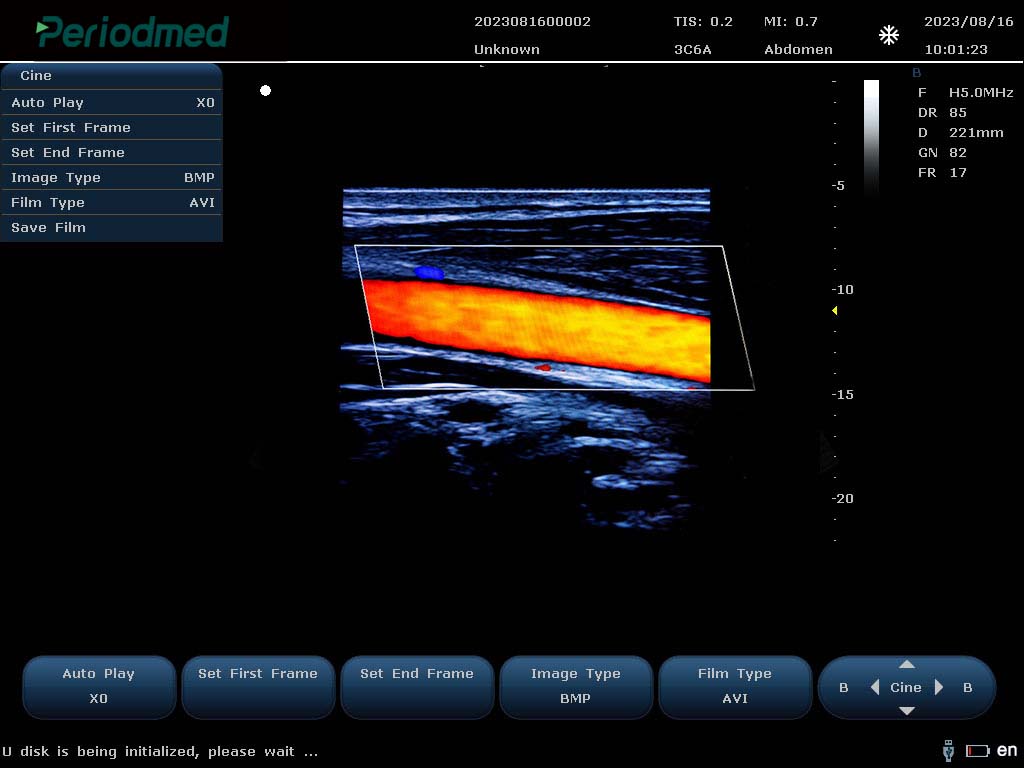

PU-L151B Portable Color Doppler Ultrasound by Yonker – Now at AdamsMed UAE & Africa (Powered by Periodmed)

Looking for a powerful and portable color Doppler ultrasound system? The PU-L151B by Yonker is the ideal diagnostic imaging solution for clinics, hospitals, and mobile healthcare providers. Now available through Periodmed and distributed by AdamsMed, this compact yet advanced ultrasound machine offers superior imaging capabilities, multi-specialty functionality, and easy mobility across Dubai, the UAE, and all African countries.

High-Resolution Imaging: Advanced imaging technology for clear visualization of organs, tissues, and vascular flow.

Color, Power & Pulse Doppler Modes: Enables accurate vascular and cardiac assessments.

15.6” HD LED Display: Foldable and anti-reflective screen for better visibility in any environment.

Multi-Frequency Probes: Supports convex, linear, transvaginal, cardiac, and other transducers.